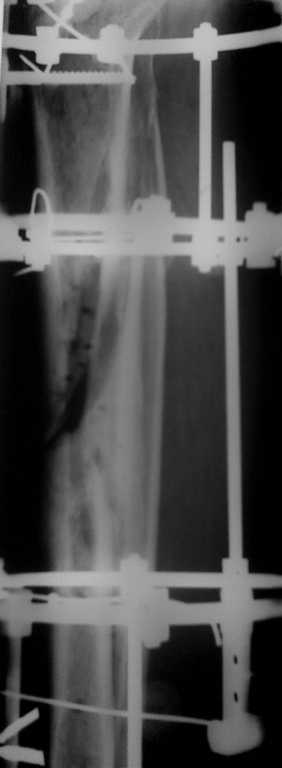

Больной получил травму около 1 года назад 24.09.07.

Обратился вовремя, но началась Белая горячка и больной на скелетном вытяжении, в общем за неделю (в свинячем поведении)повредилась клетчатка, травма кожи. Прооперировали через 14 дней после улучшения состояния, смещение устранено, стояние отломков хорошее, но появилось осложнение некроз кожи до 15см! В течение года проводилось дважды пластика кожи по Тиршу, свободным лоскутом, Тунелизация по БЕКУ. Нагружает конечность в пределах 50%, больше не хочет! На данный момент отмечается мозоль там где есть кожа. А по передней поверхности в области язвы нет. В динамики почти за год кожный дефект нарос. Что предпринять? Посоветуйте. Один хочет оперировать! Удалять дефект, но ведь нет кожного лоскута, чем укрыть?